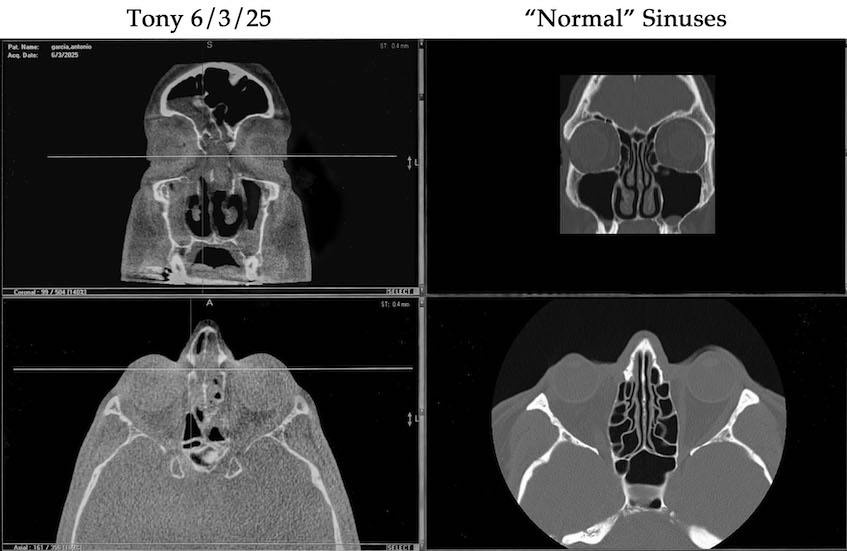

In the left column, two 2025 CT scans of the author’s sinuses (one facing head-on, one from above), showing his congestion even after operations in 1990, 2000, and 2010. This time the blockage is not mucus or saggy tissues but instead almost solely polyps. On the right, two comparative CT scans of normal sinuses from the same angle.

In early June my ENT's follow-up included a CT head scan, which confirmed the presence of a number of polyps in various sinuses—more than he could see previously with an endoscope. As an illustration I have included the visuals at right, in which I show June's scans on the left and a sample of "normal" scans on the right. The ENT said that the number and size of these polyps are what have caused the substantial mucus that has prompted my severe coughing.

The good news was—contrary to my scenarios 15, 25, and 35 years ago—congestion did not fill my sinuses (likely because I am strict about flooding my sinuses with saline when any congestion arises). And the lining of my sinuses was  not swollen and flabby and flopping into my sinus cavities (likely because I have not been as allergic the last 15 years, not causing constant cycles of swelling and shrinking of my tissues): the lining was fairly normal. So the newer problem was largely just about polyps.

Thinking back on 1990, 2000, and 2010: just prior to those operations, the major positive difference this time was that my sleeping had rarely been affected; and I breathed through my nose all the time during the day and night. That simply wasn't possible the previous three occasions; so I hadn't thought that polyps could be the cause of my recent cough issues. But the ENT's analysis, based on his scopes and scans, was convincing.